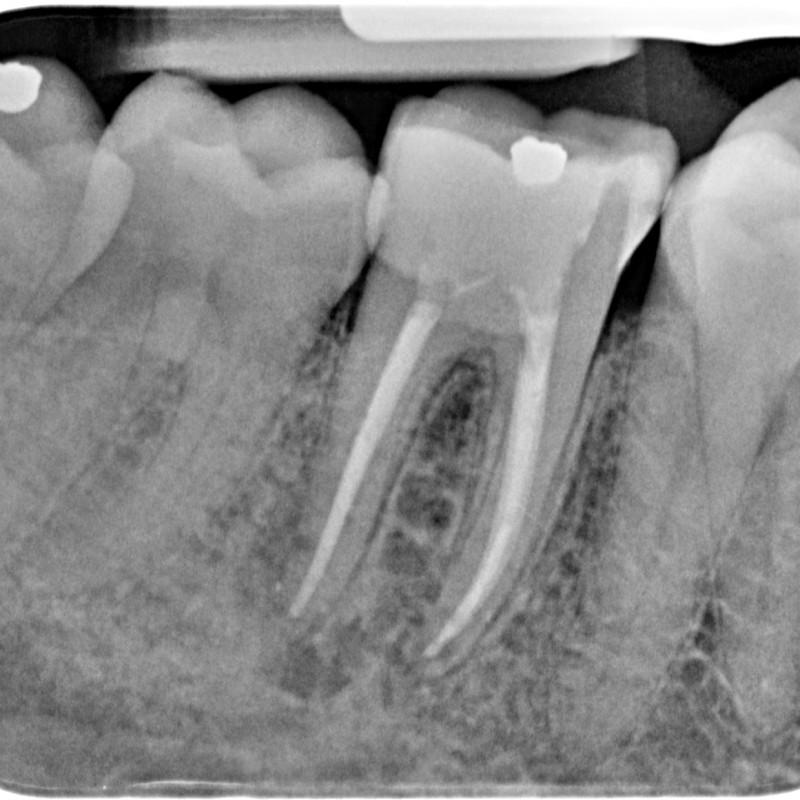

501013-08-6049-X-20150508-122214-XPZQKLSCU9AB-4